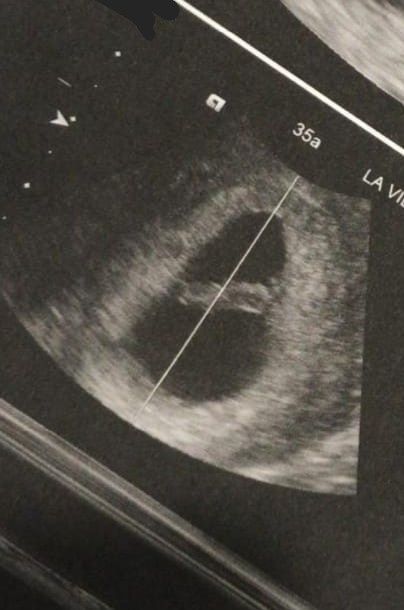

Ho caricato una foto nel post di Ilaria

2557 giorni fa

Ragazze qst è l'eco a 7 settimane di mia cugina..😍 Secondo voi cos'è?? Come va guardata? Così com'è..quindi frontale o pensando k sia messa al contrario? 🤔